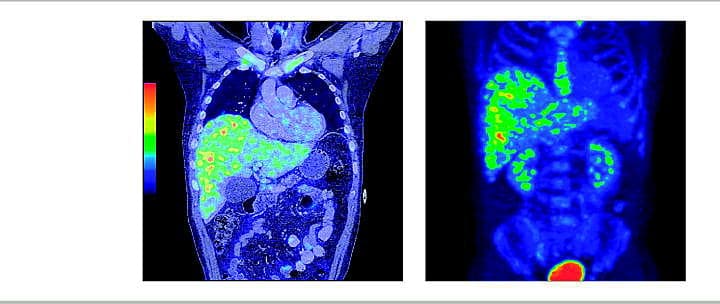

Positronemissionstomografi (PET)/computertomografi (CT) viser multiple opladende processer i leveren. Det aksiale skelet oplader pga. øget metabolisme i regenererende knoglemarv. Nyrer og urinveje oplader pga. udskillelse af traceren (18 F-deoxy-glukose).

Diagnosen hepatisk candidiasis blev stillet på baggrund af sygehistorien, de typiske blodprøver med især svært forhøjet serumbasisk fosfatase og PET/CT'en.

PET/CT har hurtigt vundet indpas til vurdering af bl.a. højmaligne lymfomer, men inflammation er en væsentlig fejlkilde inden for tumordiagnostik med PET/CT - tilfældet her kunne tolkes som levermetastaser.